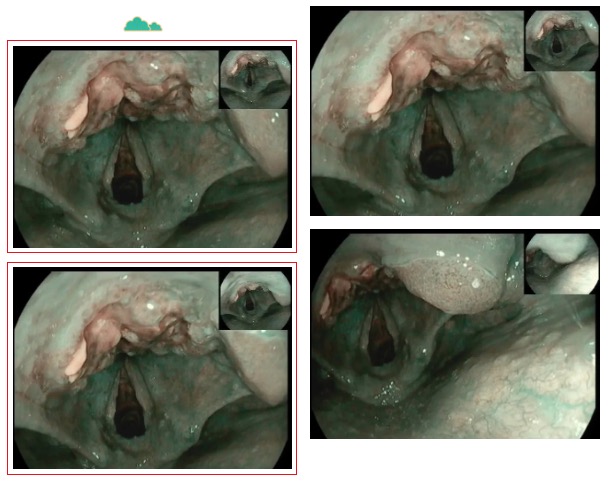

走進6診,是一位71歲急診檢查的患者,患者胃內(nèi)大量食物潴留,視野欠清,胃竇及幽門見一不規(guī)則環(huán)形腫物,腫物表面污穢不平,管腔狹窄,內(nèi)鏡無法通過,胃竇前壁見約1.5*1.2cm丘狀隆起,中央凹陷。內(nèi)鏡醫(yī)生陳大夫給予病理活檢,待病理結(jié)果出來行進一步治療。

走進7診,是一位76歲懷疑胃癌伴幽門不全梗阻的患者,同樣在胃竇、幽門處見環(huán)形不規(guī)則隆起腫物致幽門狹窄,鏡身無法通過。